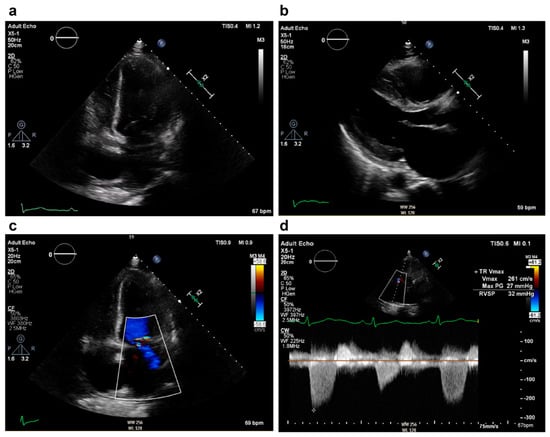

2. Case Presentation